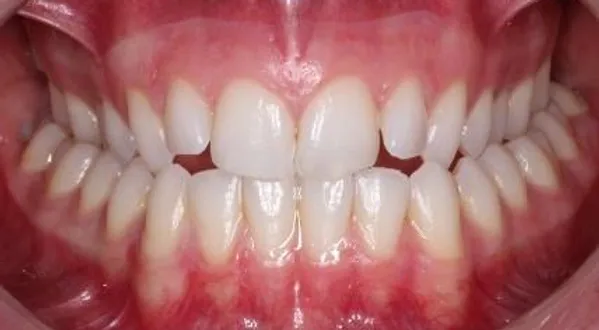

if you have bad transverse maxillary deficiency then definitely look into it. i want to try and get this however i dont know if i'll be eligible seeing as how my lower arch is like 10mm smaller than my maxillary arch.